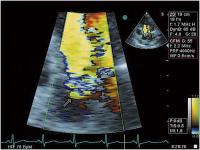

Abbildung 3: Flowkonvergenzzone oberhalb der Aortenklappe, diastolisches Farbdopplersignal im apikalen 5-Kammerblick